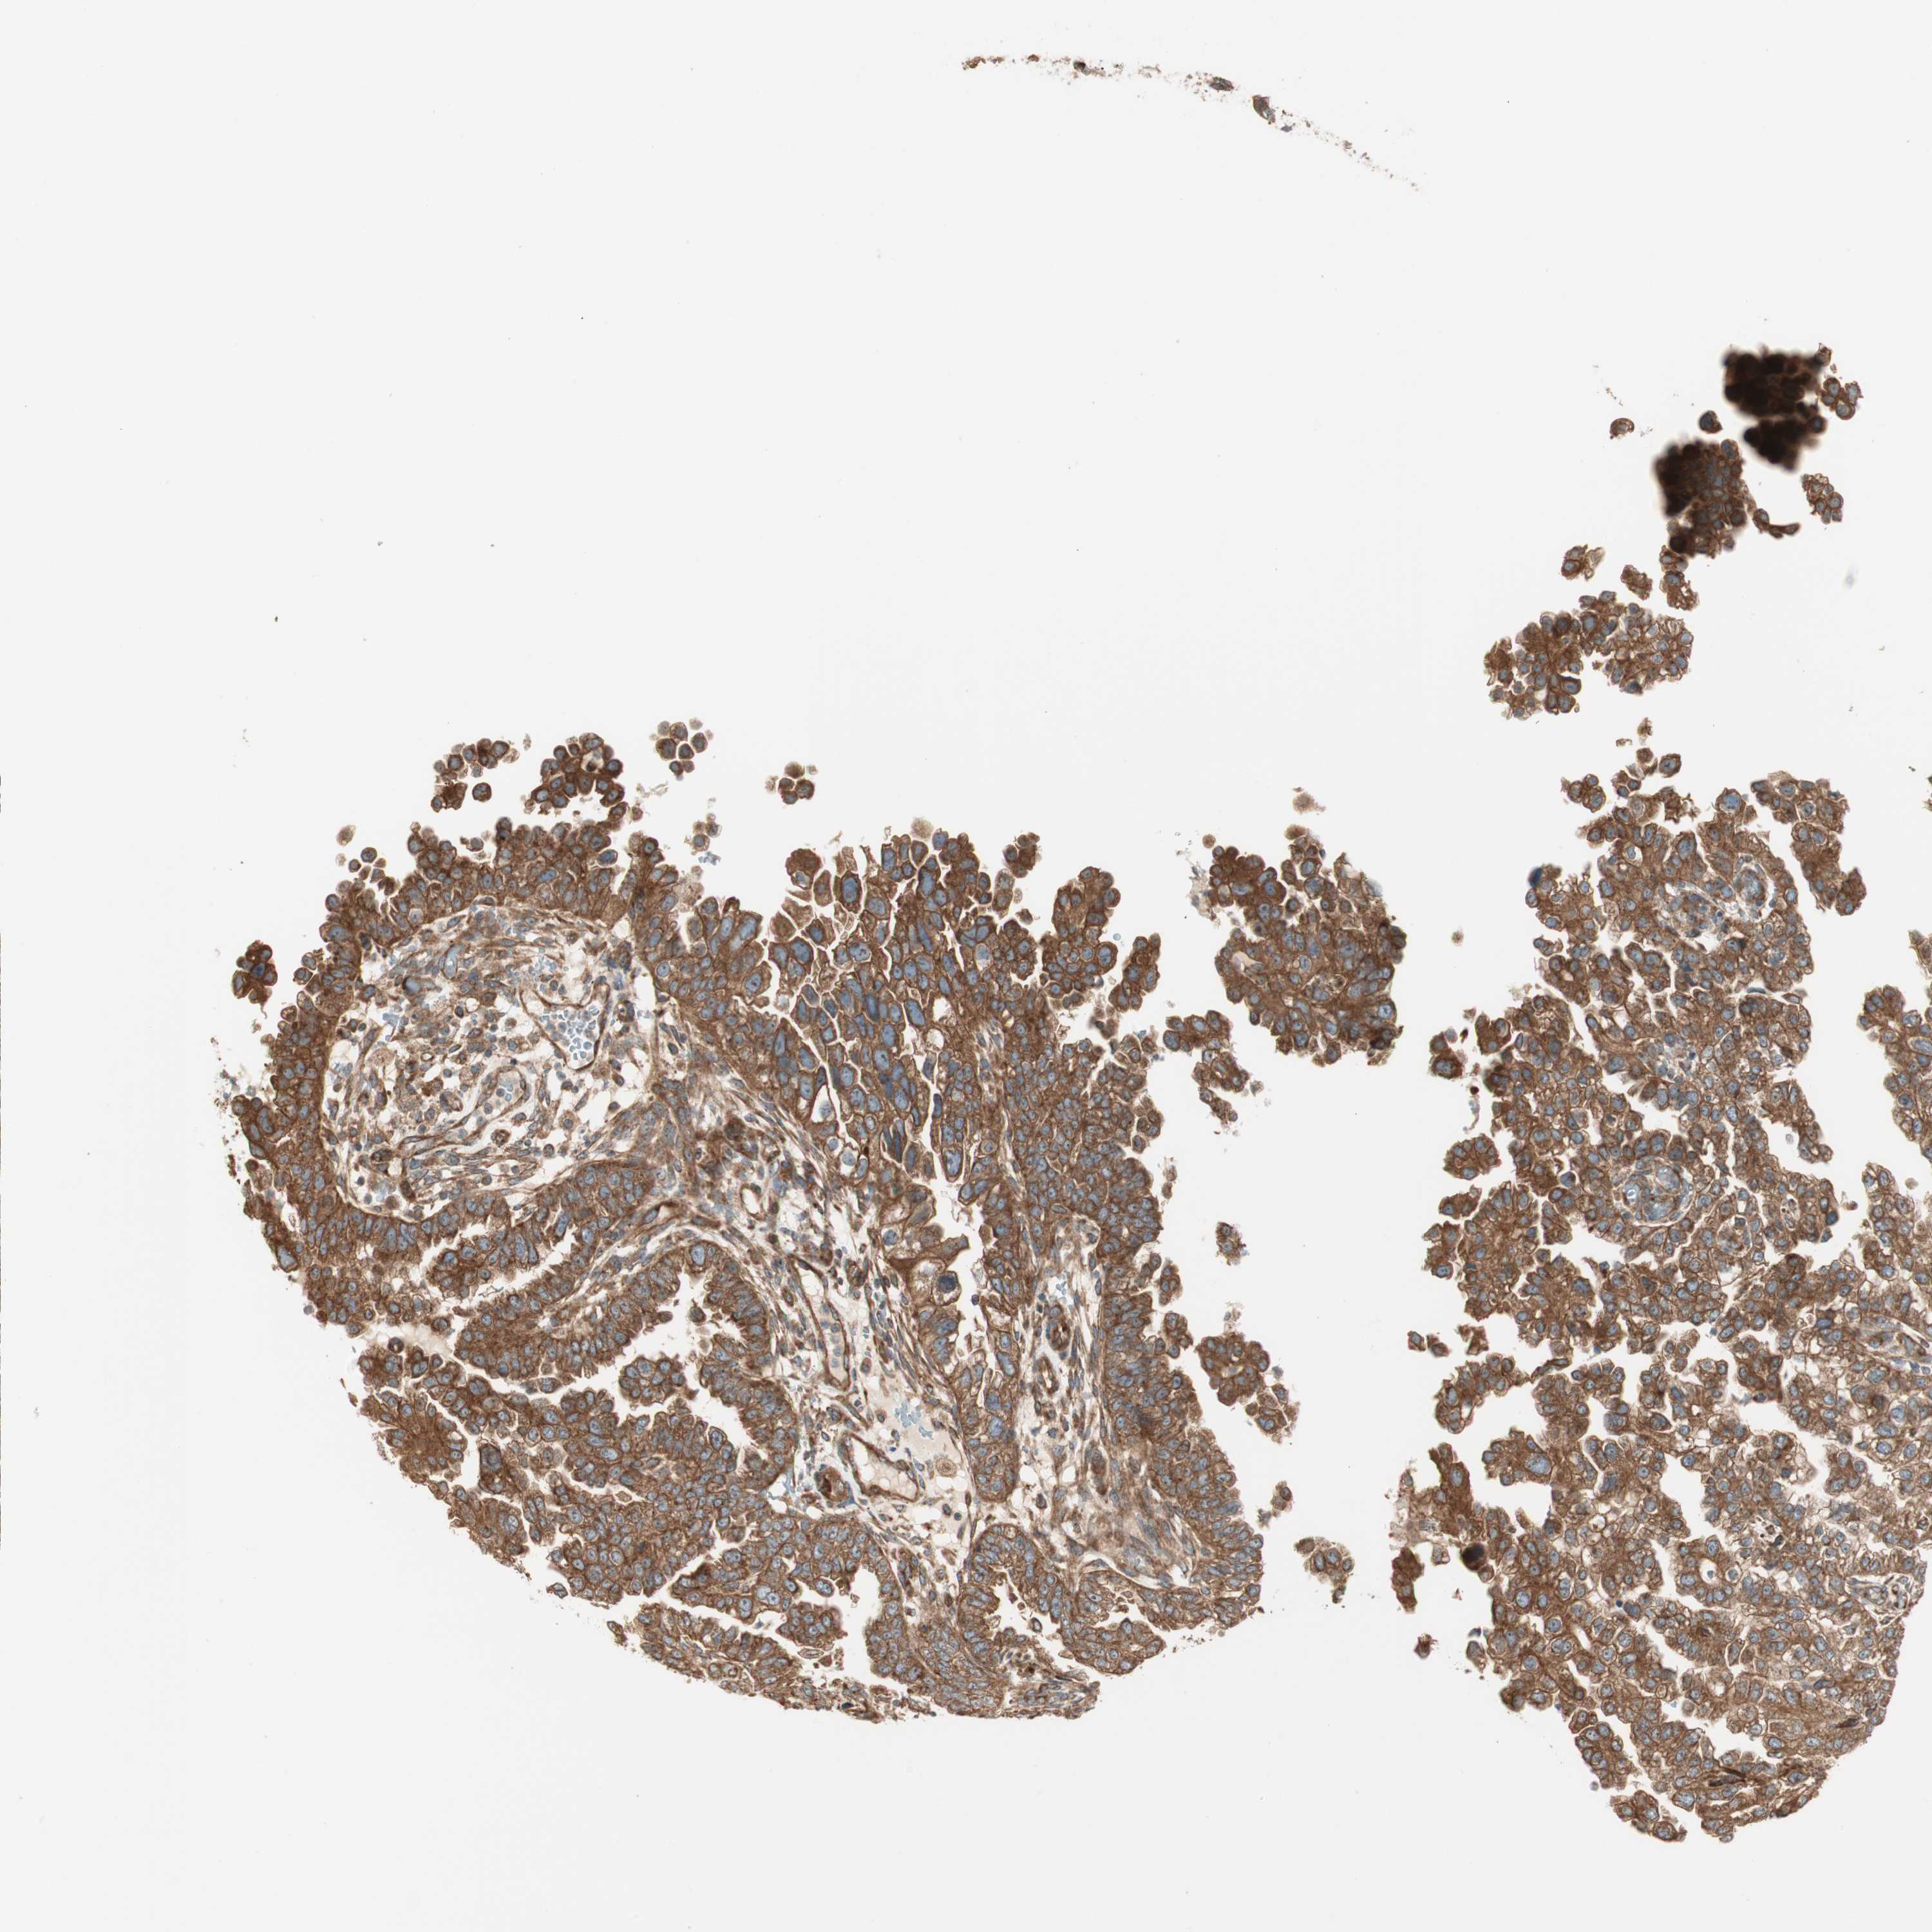

ENDOMETRIAL CANCER - Protein expressioni

A mouse-over function shows sample information and annotation data. Click on an image to view it in a full screen mode. Samples can be filtered based on level of antibody staining by selecting one or several of the following categories: high, medium, low and not detected. The assay and annotation is described here.

Note that samples used for immunohistochemistry by the Human Protein Atlas do not correspond to samples in the TCGA dataset.

Antibody stainingi

Antibody staining in the annotated cell types in the current human tissue is reported as not detected, low, medium, or high, based on conventional immunohistochemistry profiling in selected tissues. This score is based on the combination of the staining intensity and fraction of stained cells.

Each image is clickable and will lead to virtual microscopy that enables deeper exploration of all samples and also displays staining intensity scores, fraction scores and subcellular localization as well as patient and tissue information for each sample.

Antibody HPA007301

Staining

High

Medium

Low

Not detected

Intensity

Strong

Moderate

Weak

Negative

Quantity

>75%

75%-25%

<25%

None

Location

Nuclear

Cytoplasmic/membranous

Cytoplasmic/membranous,nuclear

Adenocarcinoma, NOS